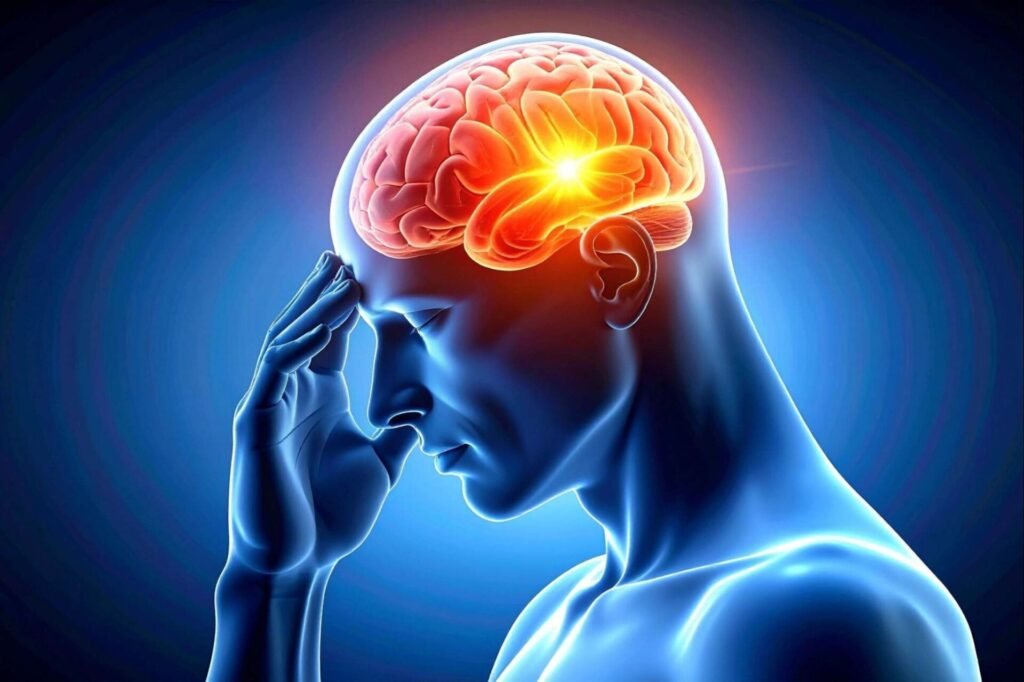

NEUROLOGICAL (Neuroinflammatory)

✅Strong evidence — Lifestyle and inflammation are key modulators

Alzheimer’s disease / dementia

(Approx. 5–7% of people >60 globally)

Chronic low-grade neuroinflammation contributes to neurodegeneration; diet, physical activity, sleep, and cognitive stimulation reduce risk and slow progression.

Multiple sclerosis (MS)

(Approx. 0.03–0.1% globally; higher prevalence in Western countries)

Autoimmune demyelinating disease; evidence supports influence of vitamin D, diet quality, exercise, and smoking cessation on disease activity.

Moderate evidence — Lifestyle may improve inflammatory burden and outcomes

Major depressive disorder / depression

(Approx. 5–6% global prevalence)

Low-grade systemic inflammation is increasingly recognised as a contributor; exercise, anti-inflammatory diets, sleep optimisation, and stress reduction improve outcomes.

Parkinson’s disease

(Approx. 0.1–0.2% globally; increases with age)

Neuroinflammation contributes to disease progression; lifestyle factors such as exercise and diet influence symptom trajectory.